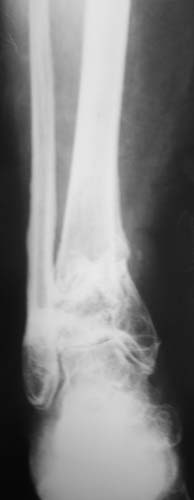

Женщина, 62 года. Травма 2 года назад в результате ДТП. Находится на лечении с 30.10.06 года с диагнозом: Несросшийся перелом дистальной трети правой большеберцовой кости с угловыми деформациями дистального отдела конечности, дефектом костной ткани.

Рубцовой деформацией мягких тканей медиальной поверхности дистальной трети голени. Нейротрофические нарушения. Посттравматический остеопороз. Дегенеративно-дистрофический остеоартроз правого голеностопного сустава.Сопутствующая патология.: ЖКБ, хронический калькулезный холецистит в стадии ремиссии. МКБ, хронический пиелонефрит в стадии ремиссии.Ожирение 3 ст. Посттромбофлебитический синдром нижних конечностей, ХВН 2 ст. Посттравматическая нейропатия левого малоберцового нерва с парезом левой стопы. Какие предложения по тактике лечения? Заранее благодарю!

Голеностопный сустав тут, видимо, потерян. Так что надо думать только про стабилизацию. Какие из существующих вариантов артродеза доступны, и какой из доступных оптимален? Антон, есть ли смысл обсуждать варианты с закрытым штифтованием, доступно оно? Если да, то Алексей Семенистый предлагает вполне жизнеспособный план (хотя можно и антгерадно сделать). Если нет, то надо что-то придумывать с аппаратом. Наверно, латеральным доступом кпереди от fibula с ее пересечением открыться, и что-то костно-пластическое делать.